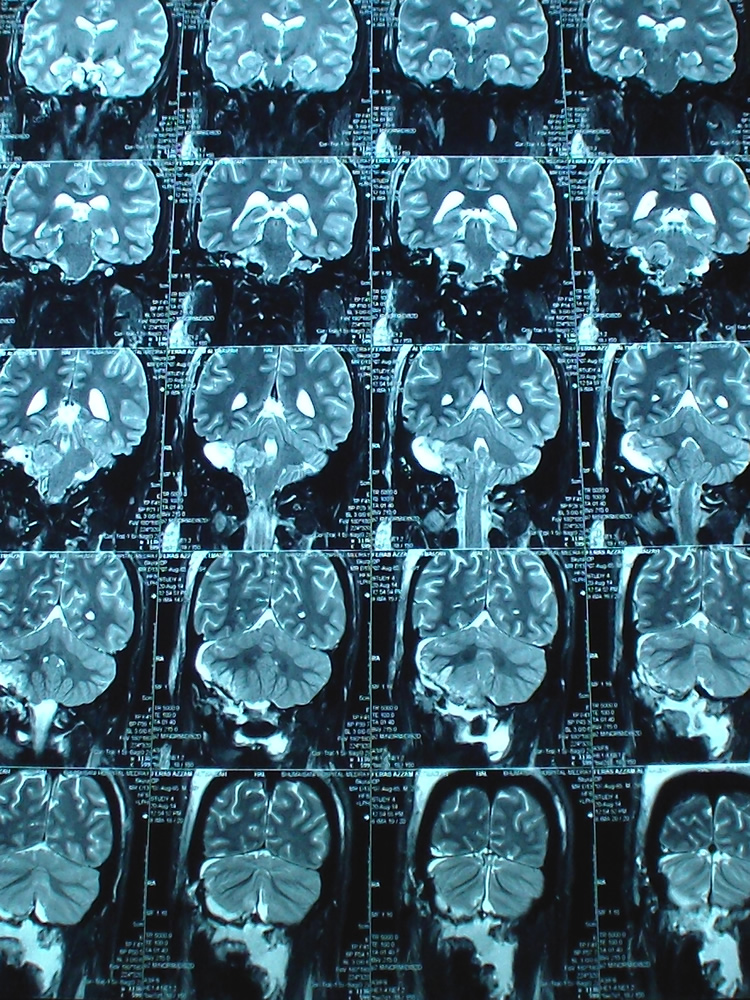

This case demonstrate that MRI must be performed at regular basis after surgery to prevent escalating complications, which could evolve several hours after surgery Fig 3-4.

Figure-4: Coronal TW2 done 2 days after surgery showing the edema, which evolved several hours after surgery.